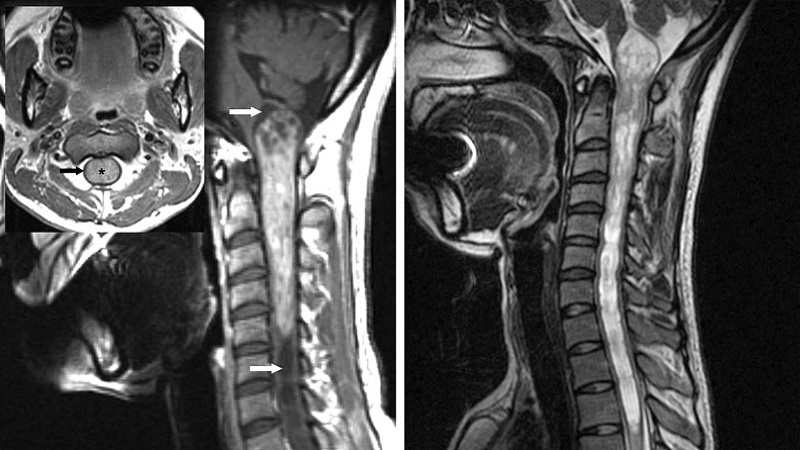

Khi chụp cộng hưởng từ, hình ảnh cho thấy một kết cấu rắn ngấm thuốc mạnh. Chúng là một tổn thương dạng nang và thường xuất hiện thêm một đường rãnh rộng ở cả hai đầu. Ở dạng u nội tủy đang xét, tủy sống bị tổn thương gần như toàn bộ nên thay vì phẫu thuật loại trừ hoàn toàn khối u, bệnh nhân sẽ được chỉ định sinh thiết và cắt bỏ một phần. Sau đó sẽ được điều trị bổ trợ bằng xạ trị để thu nhỏ kích thước phần u còn lại.

Khi chụp MRI, u nguyên bào mạch máu có hình ảnh tương tự u tế bào hình sao có lông, tức là có nang và rãnh. Tuy nhiên, chúng được phân biệt bằng sự xuất hiện của những kết cấu dạng nốt (chính là các mạch máu tăng sinh). Khi đã xác định rõ bản chất của loại u này và can thiệp bằng phẫu thuật thì cơ hội phục hồi của người bệnh là rất cao.